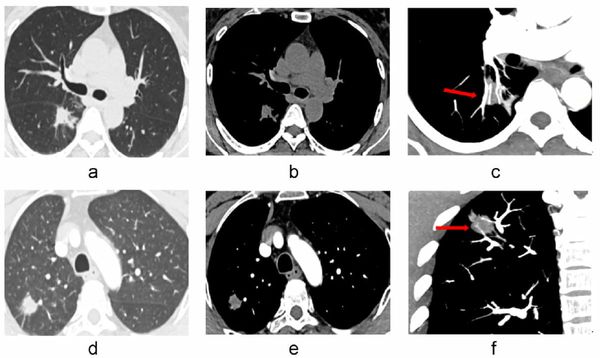

New research shows that incorporating the CT vascular sign into assessments of pulmonary nodules led to significant increases in specificity and accuracy as well as reduced false positive rates for differentiating between malignant and benign solid pulmonary nodules.